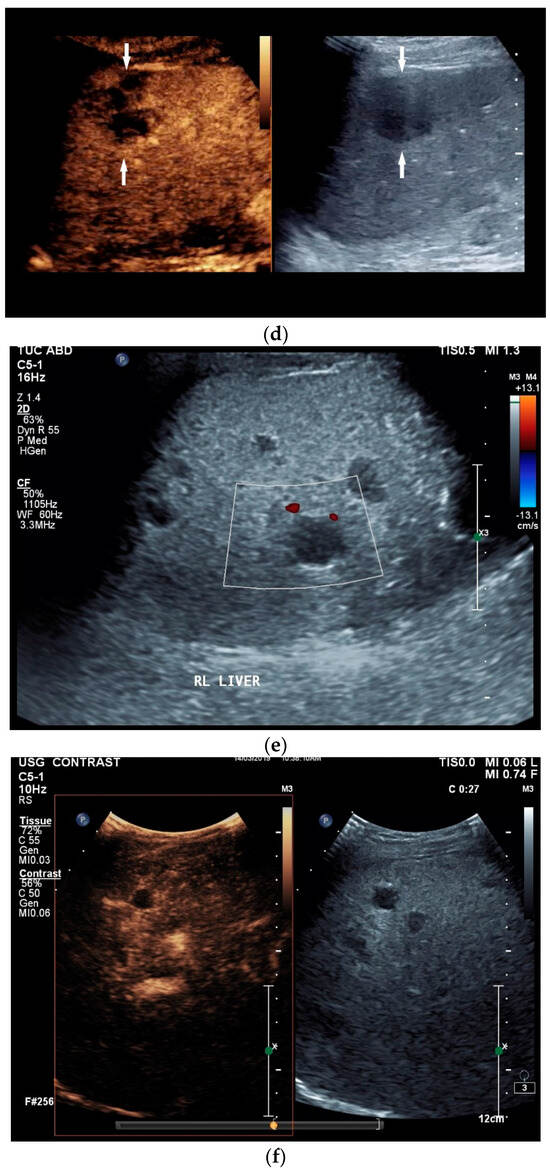

Figure 4.

Sonographic and CEUS features of splenic tuberculosis. Sonographic and CEUS features of splenic tuberculosis. Subcapsular splenic lesion (arrow) (a), subcapsular splenic lesion using a linear transducer of 12 MHz (arrows) (b). Histologically confirmed tuberculosis from mediastinal lymph nodes. Multiple small splenic lesions (c). Using CEUS with a linear transducer (9 MHz), these are slightly hypoenhanced in the arterial phase (d), and show a progressive washout in the course of the venous phase (arrows) (e). Subcapsular splenic lesion (arrow) with nonenhanced and hypoenhanced parts and hyperenhanced rims indicate a caseous necrosis (f). In another section, an interrupted spleen capsule (arrow) due to a rupture of the caseous necrosis can be assumed (g).